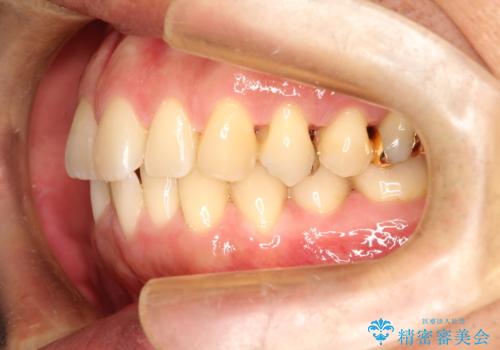

ワイヤーによる全体的ながたつきの矯正治療

- 30代男性

- メタル

- 1年3ヶ月

- 全体的ながたつきを治したいとのことで来院されました。

ワイヤー矯正とマウスピース矯正の二つの器具での治療をご案内し、ワイヤー矯正を選択されました。

インビザラインを装着するのがめんどうなので、ワイヤーの方があっているとのことで今回の治療方法を選択されました。